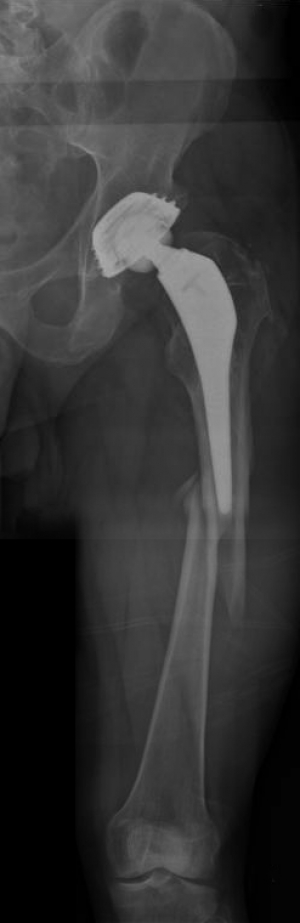

In this OTA type 32 B2 fracture the minimally invasive technique has been used, which is based on the concept of a totally closed reduction. The plate is inserted through a short 3-4cm incision.